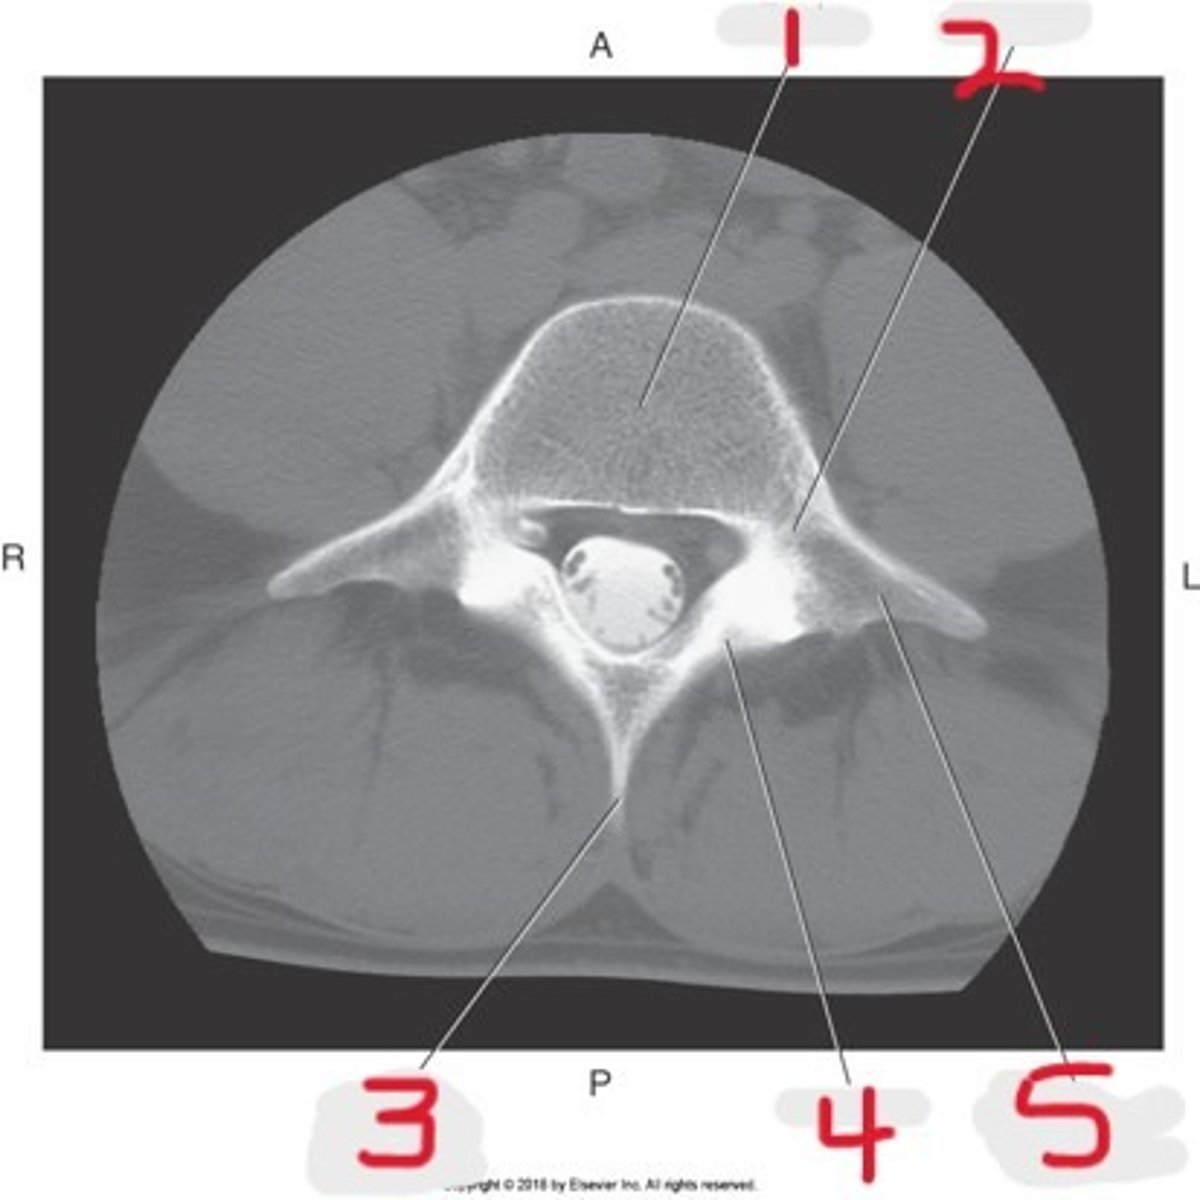

1) Body

2) Vertebral foramen

3) Lamina

4) Pedicle

5) Transverse process

6) Superior articular process

7) Spinous process

Name all numbered structures

1) Body

2) Pedicle

3) Spinous process

4) Lamina

5) Transverse process

Name all numbered structures